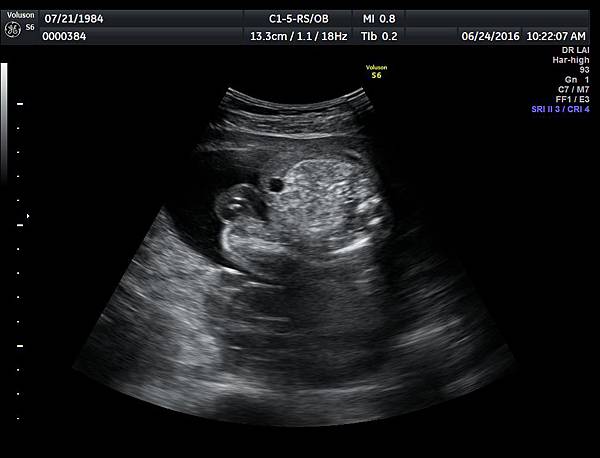

6月24日在我的診所,我幫一位懷孕22週31歲的孕婦看高層次超音波,發現胎兒的腸子很白,形狀也特別的怪( 附圖 1~12 ),我建議她做進一步相關的檢查,包括抽羊水檢查等等。